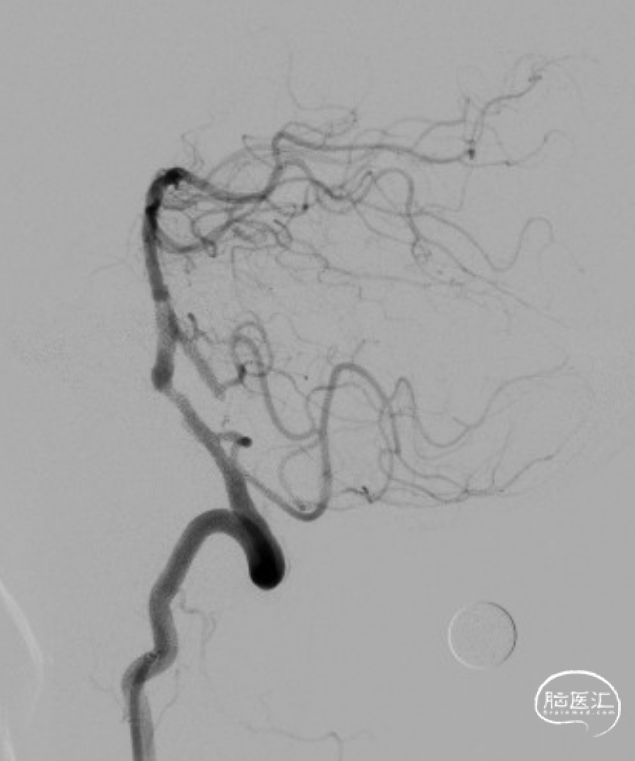

球扩后造影观察。

术后造影:RV4段狭窄较前明显改善。